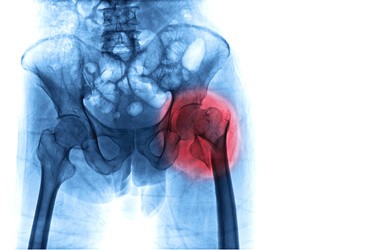

Zimą, szczególnie po intensywnych opadach czy w trakcie oblodzeń, zmienia się charakter urazów, z jakimi pacjenci trafiają na szpitalne oddziały ratunkowe. Najczęściej pojawiają się kontuzje związane z poślizgnięciem na oblodzonej lub śliskiej nawierzchni. Podczas utarty równowagi instynktownie próbujemy zamortyzować upadek poprzez podparcie się rękami, co może skutkować urazami nadgarstka i przedramion.

W tym okresie częściej dochodzi także do urazów nóg, zwłaszcza skręceń stawu skokowego czy uszkodzeń więzadeł kolana. Obrażenia te dotyczą nie tylko entuzjastów sportów zimowych, ale zdarzają się także podczas upadków na chodnikach. Nie można pominąć również urazów kręgosłupa. Upadek na plecy czy pośladki może skończyć się bólem, stłuczeniem kości guzicznej, a w skrajnych przypadkach – kompresyjnym złamaniem trzonów kręgów. Każda z tych kontuzji wymaga badań obrazowych i niesie za sobą ryzyko długotrwałego unieruchomienia.